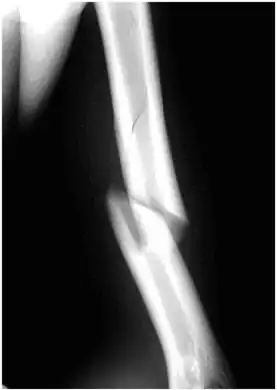

- Internal rotation view showing a spiral fracture at junction of middle and distal thirds of humerus.